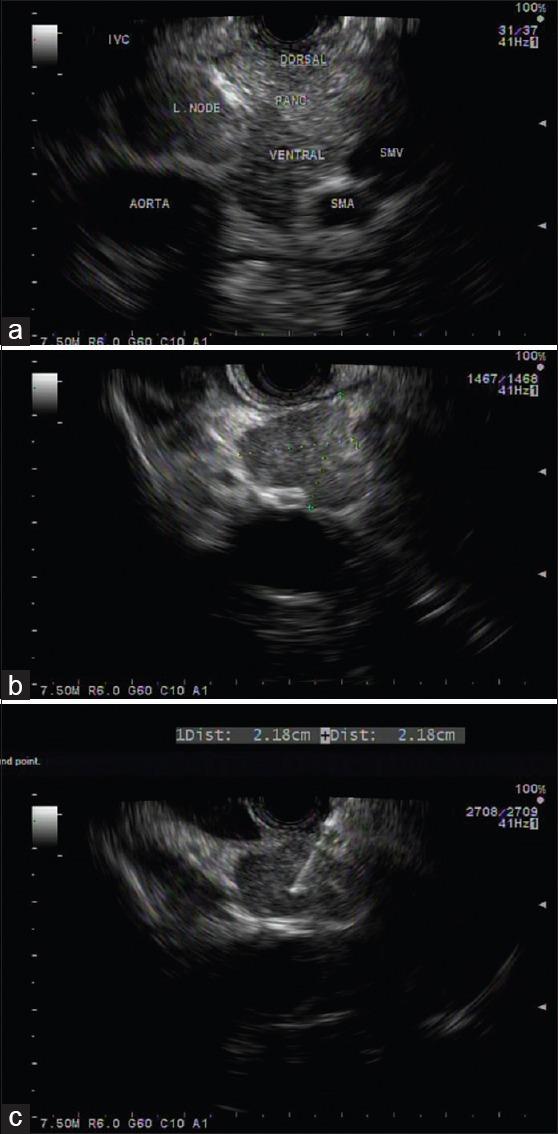

Tissue acquisition using EUS has considerably evolved since the first EUS-FNA was reported 25 years ago. Its introduction was an important breakthrough in the endoscopic field. EUS-FNA has now become a part of the diagnostic and staging algorithm for the evaluation of benign and malignant diseases of the gastrointestinal tract and of the organs in its proximity, including lung diseases. This review aims to present the history of EUS-FNA development and to provide a perspective on the recent developments in procedural techniques and needle technologies that have significantly extended the role of EUS and its clinical applications. There is a bright future ahead for EUS-FNA in the years to come as extensive research is conducted in this field and various technologies are continuously implemented into clinical practice.